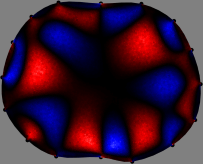

The sensitivity matrix is pre-computed assuming a homogeneous conductivity distribution in the imaging plane (Fig. 2). The numbers of rows and columns of are 208 and , respectively. For simplicity, we used a 2D forward model of the cross-section to compute . The th column of comprises the changes in the voltage data subject to a unit conductivity change in the th pixel .

To explain the FER method, we closely examine the correlations among column vectors of the sensitivity matrix , described in Fig. 2. The correlation between and can be expressed as

for [23]. This shows that the column vector is like an EEG (electroencephalography) data induced by dipole sources with directions at locations . Given that two dipole sources at distant locations produce mutually independent data, the correlation between and decreases with the distance between and . Fig. 2 shows a few images of the correlation as a function of for four different positions . The correlation decreases rapidly as the distance increases. In the green regions where the correlation is almost zero, is nearly orthogonal to .

Fig. 2 shows that if and are far from each other, the corresponding columns of the sensitivity matrix are nearly orthogonal. This somewhat orthogonal structure of the sensitivity matrix motivates an algebraic formula that directly computes the local ensemble average of conductivity changes at each point using the inner product between changes in the data and a scaled sensitivity vector at that point: